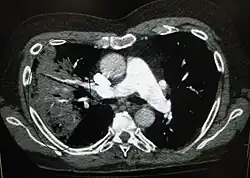

A chest radiograph is frequently used in diagnosis.[23] In people with mild disease, imaging is needed only in those with potential complications, those not having improved with treatment, or those in which the cause is uncertain.[23][69] If a person is sufficiently sick to require hospitalization, a chest radiograph is recommended.[69] Findings do not always match the severity of disease and do not reliably separate between bacterial and viral infection.[23]

X-ray presentations of pneumonia may be classified as lobar pneumonia, bronchopneumonia, lobular pneumonia, and interstitial pneumonia.[75] Bacterial, community-acquired pneumonia classically show lung consolidation of one lung segmental lobe, which is known as lobar pneumonia.[42] However, findings may vary, and other patterns are common in other types of pneumonia.[42] Aspiration pneumonia may present with bilateral opacities primarily in the bases of the lungs and on the right side.[42] Radiographs of viral pneumonia may appear normal, appear hyper-inflated, have bilateral patchy areas, or present similar to bacterial pneumonia with lobar consolidation.[42] Radiologic findings may not be present in the early stages of the disease, especially in the presence of dehydration, or may be difficult to interpret in the obese or those with a history of lung disease.[24] Complications such as pleural effusion may also be found on chest radiographs. Laterolateral chest radiographs can increase the diagnostic accuracy of lung consolidation and pleural effusion.[41]

A CT scan can give additional information in indeterminate cases[42] and provide more details in those with an unclear chest radiograph (for example occult pneumonia in chronic obstructive pulmonary disease). They can be used to exclude pulmonary embolism and fungal pneumonia, and detect lung abscesses in those who are not responding to treatments.[41] However, CT scans are more expensive, have a higher dose of radiation, and cannot be done at bedside.[41]